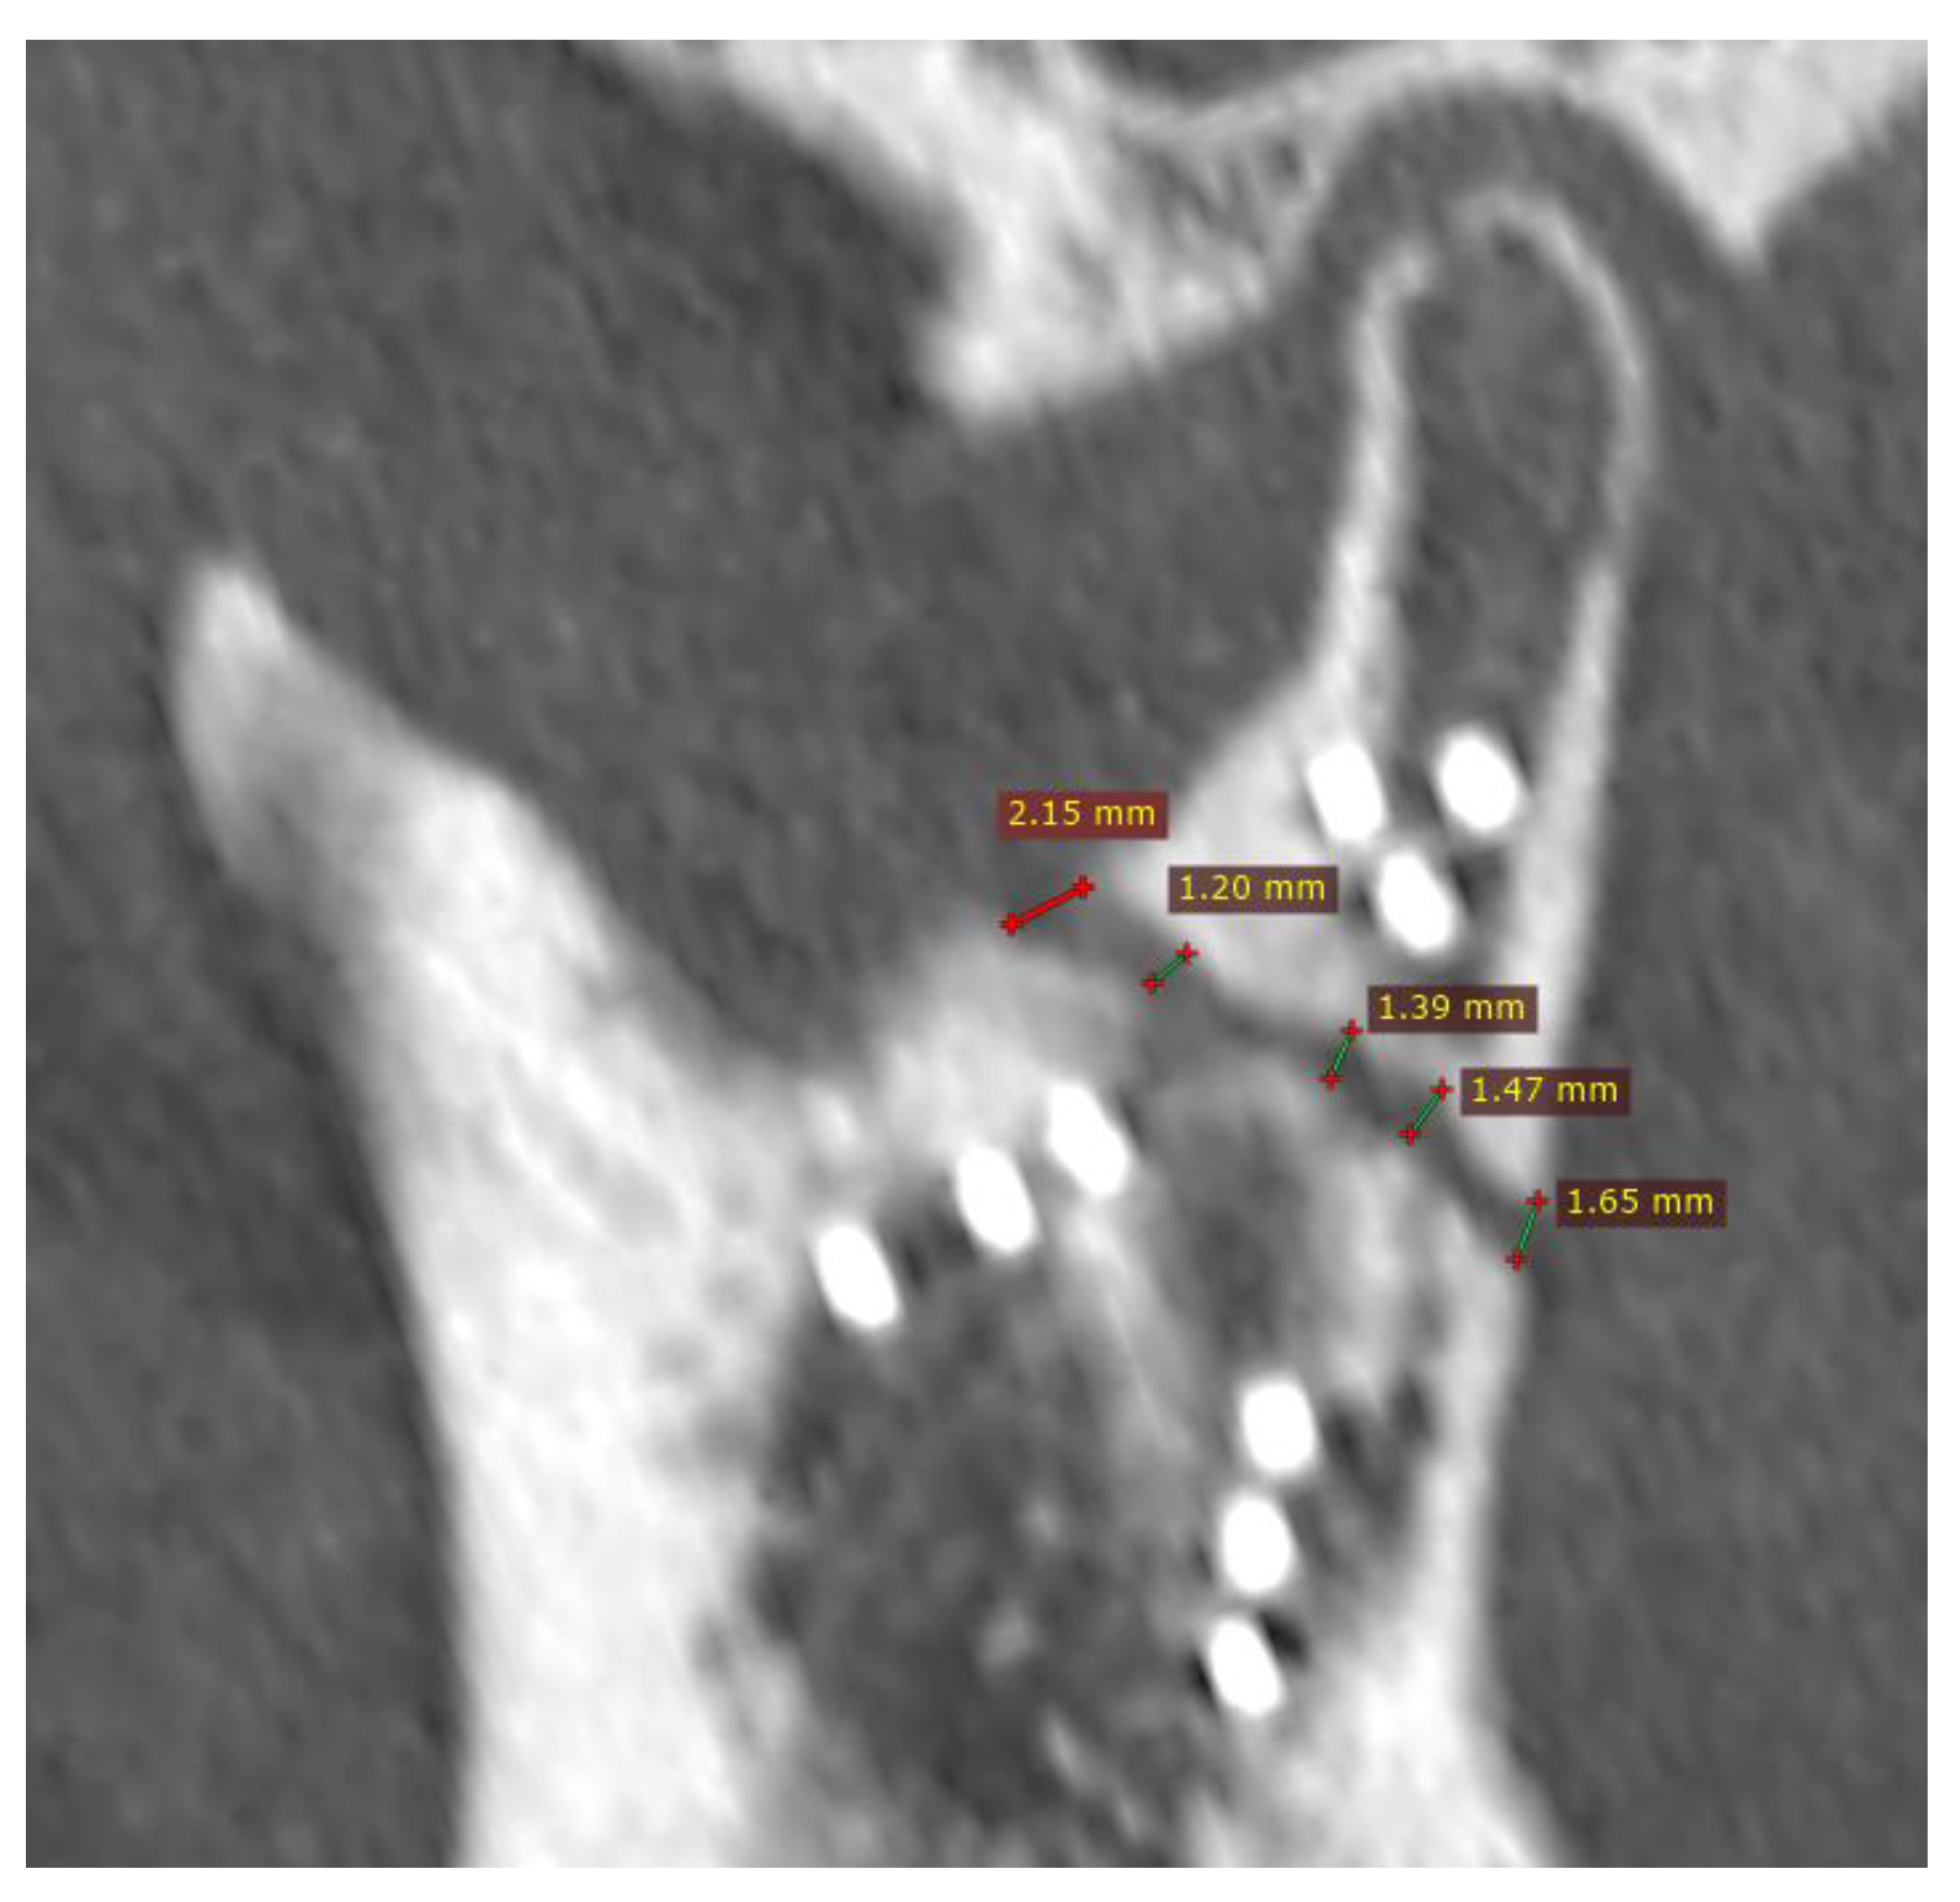

Figure 2. Fixation with incorrect reduction (CT scan immediately post-operational). Despite fixation with nine screws and the proper head position in the glenoid fossa, load-bearing osteosynthesis was created (this probably caused the plate to break when the patient began masticating hard foods in fourth month post-op). This is the result of a wide fracture gap. The distance between the bone fragments ranges from 1.2 mm to as much as 2.15 mm. It is believed that during fixation of the condylar process after a recent fracture, the gap should be reduced to less than half a millimeter, and ideally to a hairline width. Then, load-shearing osteosynthesis can be expected. It is much more reliable than load-bearing.